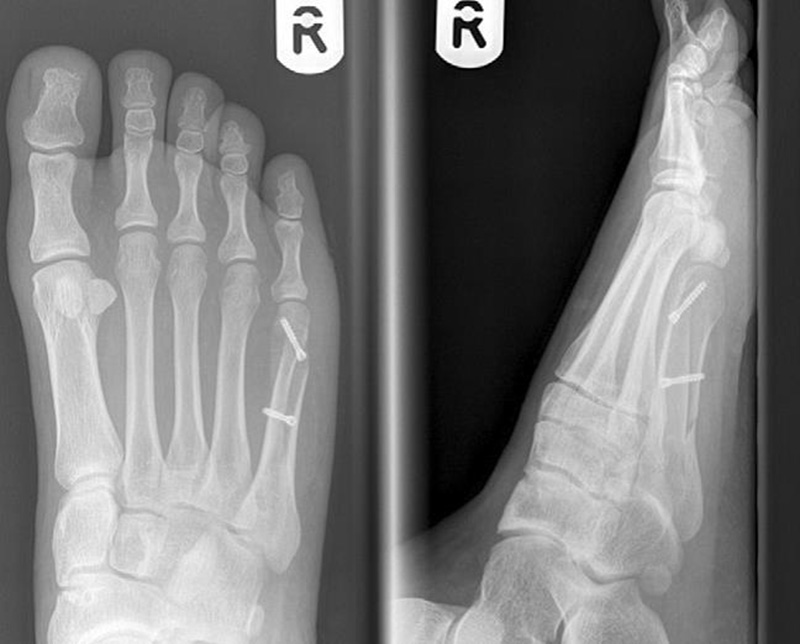

Abb. 12a: Typ III Deformität präoperativ im belasteten dp Röntgenbild.

Abb. 12b: Dorsoplantare Röntgenkontrolle nach medial schließender Osteotomie mit Schraubenosteosynthese.

Abb. 12c: Schrägaufnahme nach medial schließender Osteotomie mit Schraubenosteosynthese.

Abb. 12d: Seitliche Aufnahme nach medial schließender Osteotomie mit Schraubenosteosynthese.